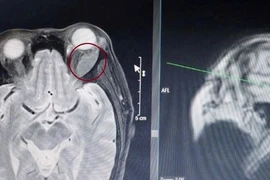

U hốc mắt tuy hiếm gặp, triệu chứng lâm sàng không đặc hiệu nhưng có thể gặp ở tất cả mọi người. U dễ gây tổn thương dây thần kinh, mạch máu gây giảm thị lực và mù lòa... nên cần phát hiện sớm.